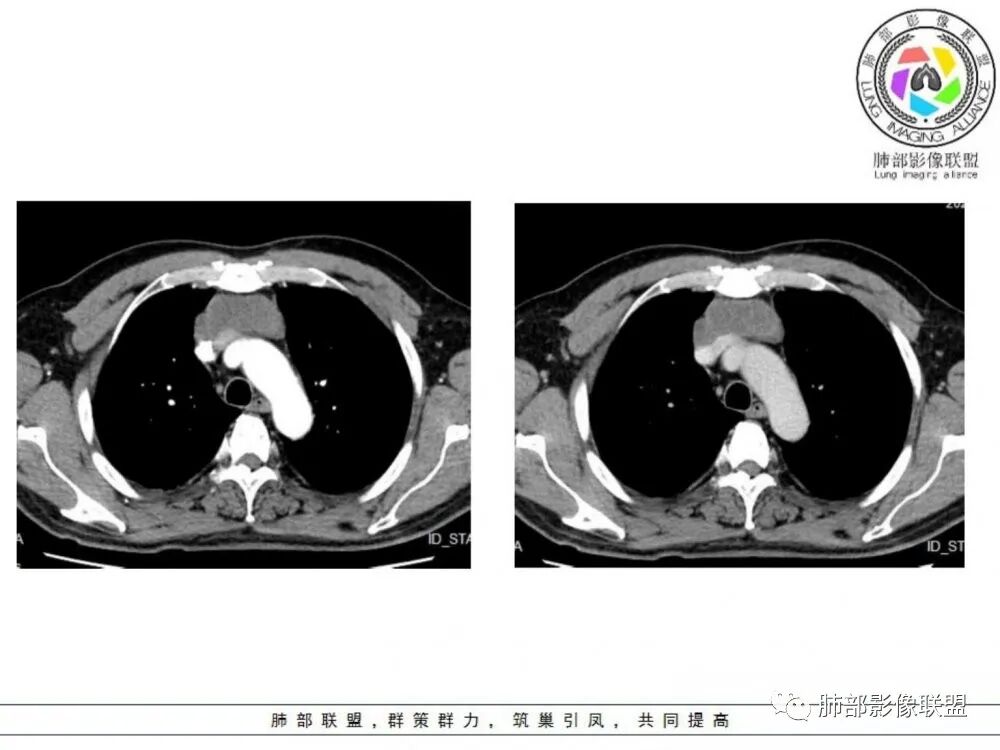

中老年男性,前纵隔占位,基本居中,向两侧生长;边缘膨隆分叶,部分边界不清,增强不均匀轻中度强化,坏死区边界不清;周围多发增大淋巴结,考虑恶性。主要在胸腺癌、胸腺瘤、淋巴瘤之间鉴别。病灶偏软,有钻缝样生长,这些征象偏向于淋巴瘤。但此例老年患者,病灶内有点状钙化,缺乏结节堆砌感,倾向胸腺癌诊断。

1、淋巴瘤:年龄跨度大,多发淋巴结肿大,融合成团,轻中度强化,约1/3可见胸腔、心包积液。多结节融合是其特点,多伴有中纵隔淋巴结肿大,包绕血管。

2、侵袭性胸腺瘤:肿块与纵隔诸器官脂肪间隙消失,血管变形移位,可见心包积液,胸膜受累类似胸膜间皮瘤。

前纵隔胸腺区分叶状软组织肿块影,轻度不均匀强化,中心可见坏死,边缘不清,病灶与邻近心包见条索影,上腔静脉受侵,上纵隔多发小淋巴结,考虑胸腺鳞癌可能。

老年男性,前纵隔不规则软组织肿块影,密度欠均匀,与大血管分界欠清,上腔静脉局部包绕受侵,增强扫描不均匀轻度强化,PET-CT高代谢。考虑恶性肿瘤性病变,胸腺癌可能。鉴别淋巴瘤。

前纵隔胸腺区肿块,边缘见分叶,病灶与周围血管分界不清,增强扫描轻度强化,pet高代谢,考虑胸腺恶性病变,胸腺癌。鉴别淋巴瘤。